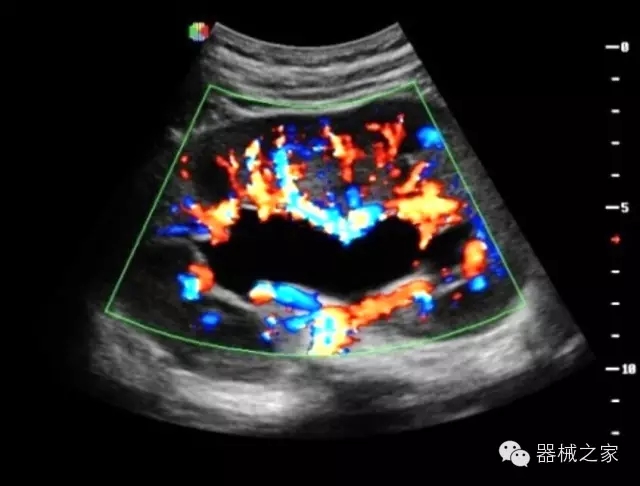

臨床圖片賞析

·獨(dú)有的RF平臺提高微小細(xì)節(jié)顯示、圖像對比度和邊界清晰度;

·特有的XCEN探頭,超寬的帶寬,表現(xiàn)更高分辨率和對比度;

·單晶純凈波探頭提供更佳的穿透力和彩色敏感度;

·獨(dú)有RF敏感血流使得心臟血流完美呈現(xiàn);